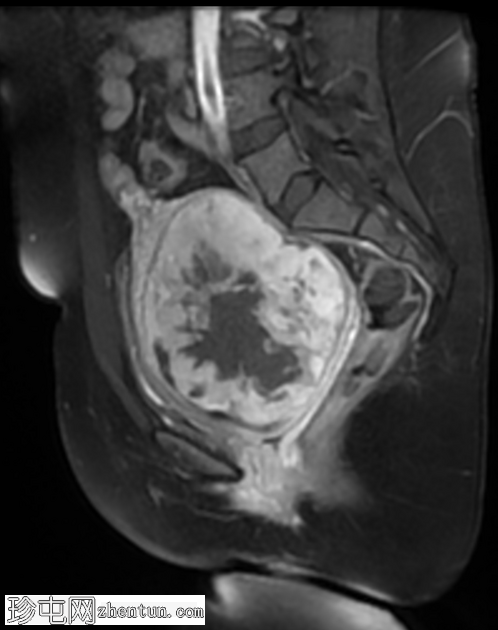

矢状位

T2

宫颈后壁及子宫下段中心可见一约11.5 × 10 × 10厘米的不规则局灶性病变。该病变在T1脂肪饱和图像上呈等信号,伴有一偏心低信号区,中心有一细微高信号,提示有出血。

在T2加权图像上,病变呈中高信号,伴有囊性变性区域,以及与T1暗区相对应的偏心T2暗信号,也与含铁血黄素相符。

病变显示弥散受限区域,DWI信号强度高(等于或高于子宫内膜),实体强化区域ADC映射信号低,测量值小于0.9×10⁻³ mm²/秒(约0.755×10⁻³ mm²/秒)。

注射造影剂后,病变实体部分呈现均匀强化。

肿块对邻近结构产生显著的占位效应,向前压迫膀胱。膀胱呈空虚状态,Foley导尿管位于原位。

印象:放射学特征高度提示平滑肌肉瘤;有必要进一步评估